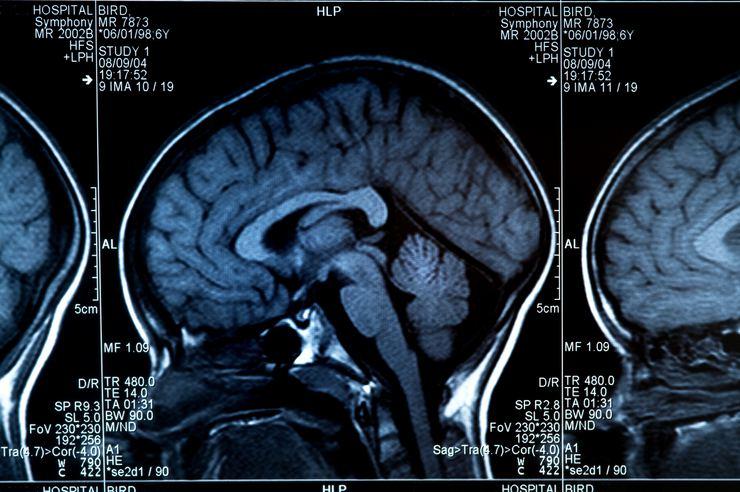

- Günümüzde baş döndürücü bir hızla artan bilimsel gelişmeler sayesinde tıp biliminde de müthiş yenilikler oldu. Bu yenilikler sayesinde ortalama yaşam süresi gelişmiş ülkelerde 80-90 yıla kadar ulaştı. Artmış olan ortalama yaşam süresi sonucunda, yaşlı grubun hastalıklarının da sıklığı arttı.

- Eskiden çoğumuzun hiç duymadığı Alzheimer hastalığı, Parkinson hastalığı, beyin damar hastalıkları gibi hastalıklar artık magazin basınında bile en sık konuşulan konulardan oldu. Bu hastalıkların bu denli artışında, yaşam süresinin artmasının yanı sıra modern yaşamın getirdiği birtakım olumsuzluklar da göz ardı edilemez.